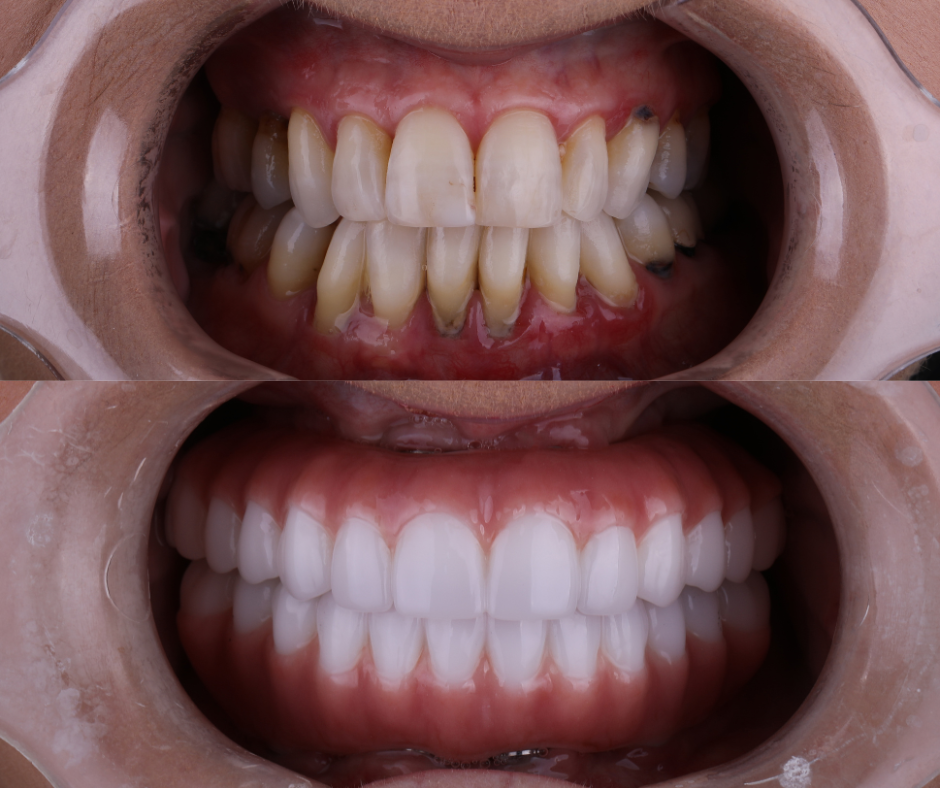

Example transformations achievable with dental implants

Dental implants are the only tooth replacement

option that prevents bone loss.

Missing tooth roots leads to long term bone loss. As the jaw(s) shrink, facial sagging, and advanced aging occur.

Dental implants are the only solution that stops this process. Traditional dentures and bridges fall short.